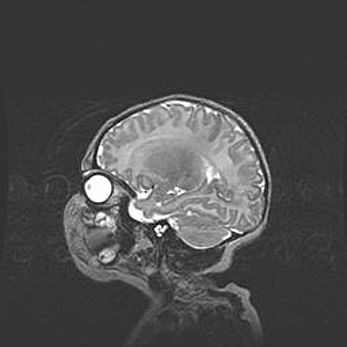

Аномалия Денди-Уокера. Признаки гипоплазии мозолистого тела.

Возраст: 5 месяцев 3 дня

Вес: 5550 г

Пол: мужской

Окружность головы: 39 см

Срок гестации: 40 недель

Аномалия Денди-Уокера – это порок развития головного мозга, для которого характерна триада симптомов: гипотрофия или аплазия червя мозжечка и/или полушарий мозжечка, расширение четвёртого желудочка с формированием ликворной кисты задней черепной ямки, гипертензионная гидроцефалия различной степени.

Гипоплазия мозолистого тела относится к дефектам внутриутробного этапа развития мозговой ткани, возникающим в процессе закладки структур головного мозга, что происходит на начальных этапах развития эмбриона.